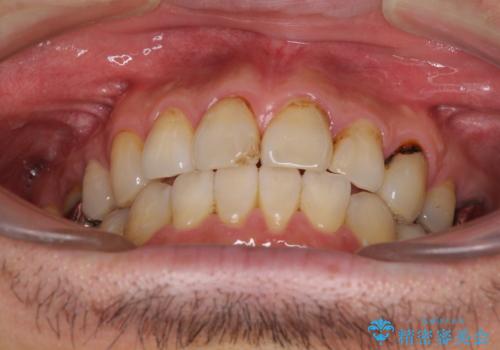

- むし歯による奥歯の痛みを気にして来院された患者様です。

神経にまでむし歯の及んでいる歯や、既に根管治療がされている歯に痛みがあったため、まずは根管治療を行うこととしました。

その後、以前行った抜歯矯正の後戻りをインビザライン・ライトにより改善し、むし歯や銀歯はオールセラミッククラウンにて補綴治療することとしました。